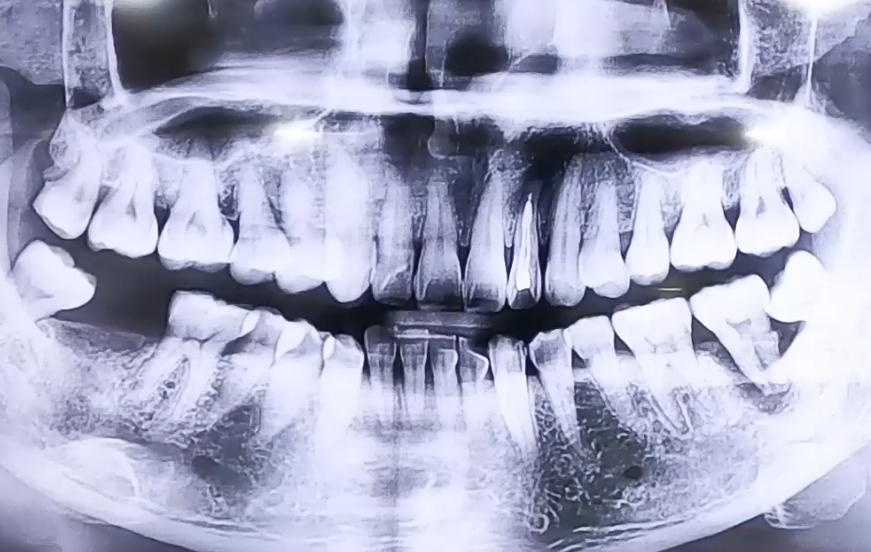

AFTER

이에 통증의 원인인 염증 부분의 치아와 사랑니를 발치하고

빈 상태였던 오른쪽 아래 어금니와 왼쪽 발치한 어금니 자리에

임플란트 식립을 하여 어금니의 기능을 복원해 드렸습니다.

추후 보철까지 완성해드리면 예쁘고 튼튼한 어금니를 가질 수 있으실 것입니다 ^^